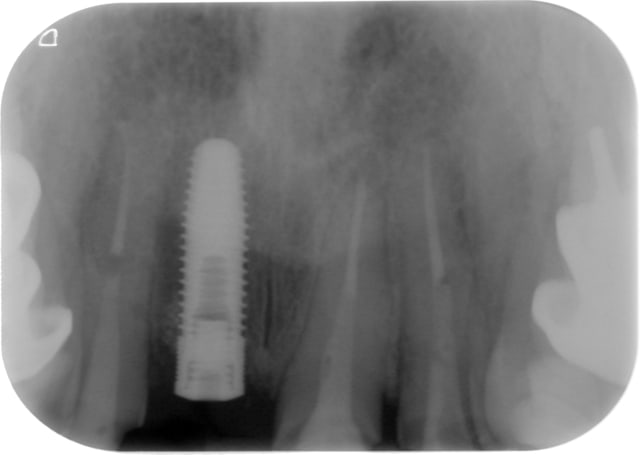

NB: sur les dents voisines on voit des provisoires réalisées le jour même pour me guider dans le positionnement tridimensionnel de l'implant, en aucun cas ce ne sont les provisoires d'usage.)

pour l'implant sur 11, ce jour:

pas de douleur

-pas de mobilité

-gencive " propre"

je vous laisse les clichés.

sur les photos, la gauche et la droite sont inversées

Super si la 13 est en cause, cela ne remet pas en question ton plan de traitement. D 'autant plus que sur ton premier cliché , la 12 ne semble pas fracturée, temporise , si tout s'estompe,

c'est O.K. Impec. D ' autant plus que je trouvais ton implant super bien placé. Attend un peu avant de déposer le tenon de la 12.